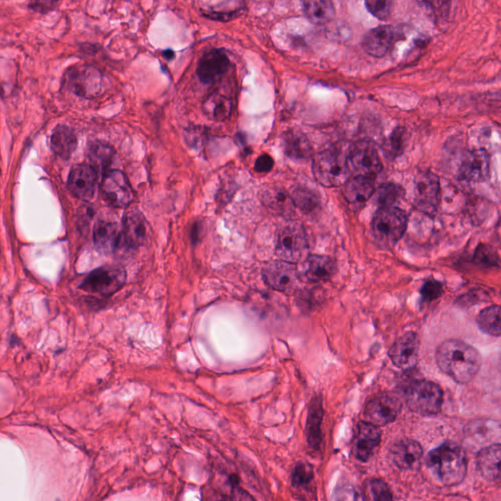

As an essential part of digital pathology, histopathology image analysis is playing increasingly important role in cancer diagnosis, which can provide direct and reliable evidence to diagnose the grade and type of cancer. This paper deals with nuclei segmentation, an important step in histopathological image analysis. The purpose of nuclei semgentation is not only counting the number of nuclei but also obtaining the detailed information of each nucleus. So unlike nuclei detection, here the outputs are the contour of each nucleus instead of only the position of their central points. Hence we can exactly extract each nucleus from the image and make it available for further analysis. For example, the features of the individual nucleus and the distribution of nuclei clusters can be used to grade and classify status of breast cancers [3, 4]. Because of appearance variation such as color, shape, and texture, nuclei segmentation from histopathological images could be very challenging, as illustrated in Fig.1, in which it is very challenging even for human to recognize and segment all nuclei within the images. Fig.1(a) and Fig.1(b) illustrate two histopathological images from different organs. Fig.1(c) and Fig.1(d) are two histopathological images from same organ but have different cancer grade.